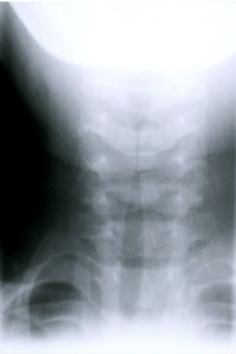

12

Qu’observe-t-on à la radiographie d’une laryngite?

Effilement de la région sous-glottique